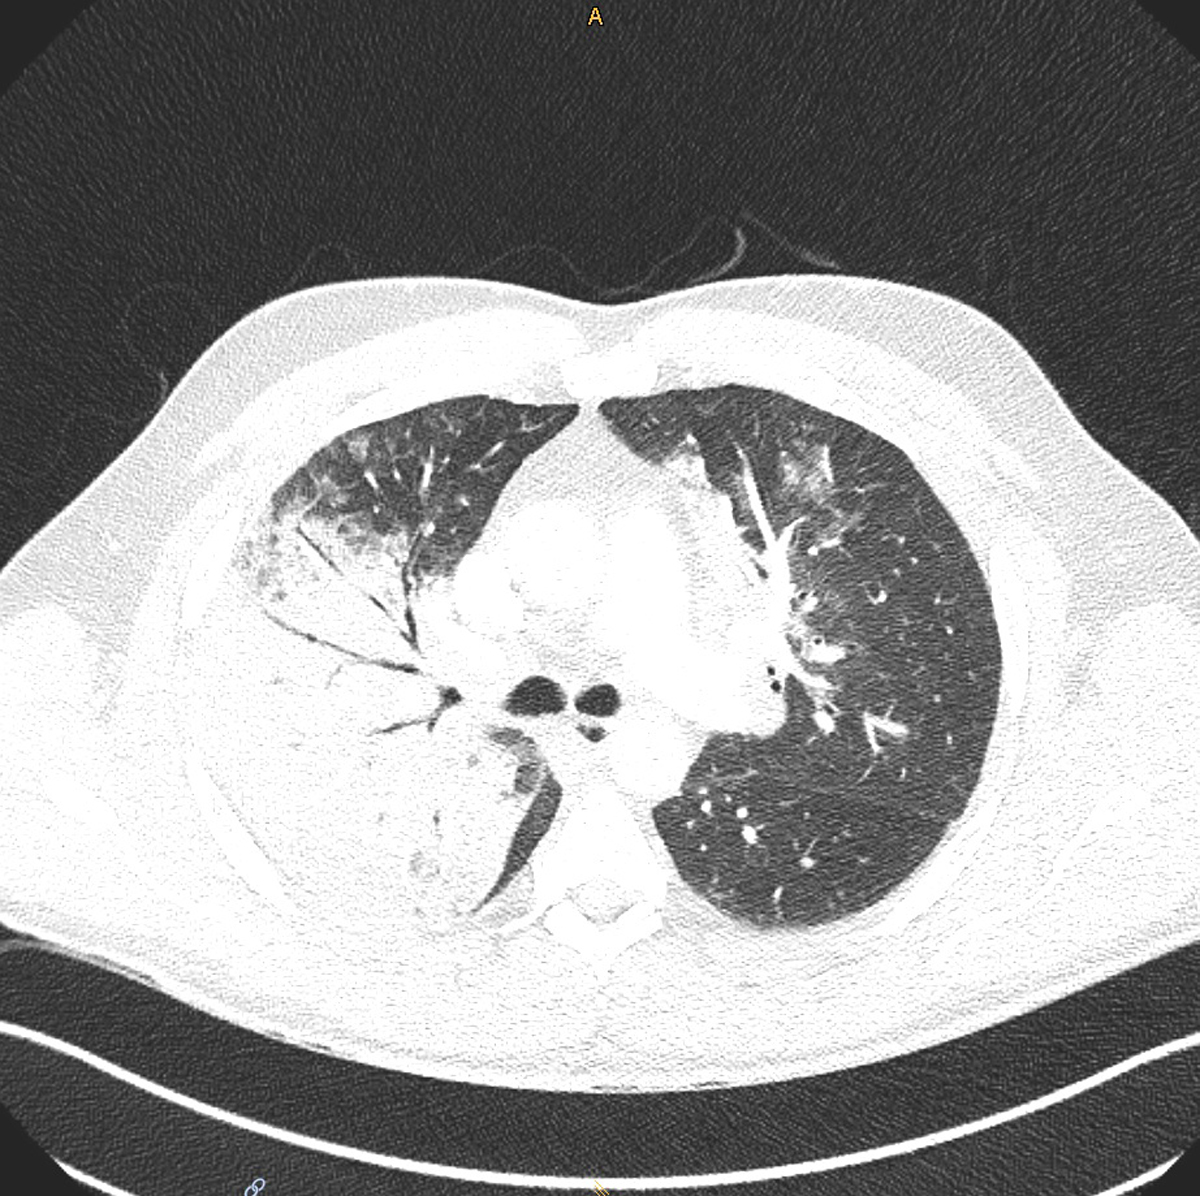

In December 2020, a 52‑year‑old man with an unremarkable medical history presented to his primary care doctor with a 7‑day history of fever and dry cough. Polymerase chain reaction testing (PCR) of a nasopharyngeal swab was negative for SARS‑CoV‑2. Symptoms were treated with acetaminophen and a short-acting bronchodilator. During the following days, self-measured oxygen saturation repeatedly dropped to a minimum of 84%, which prompted the patient to present to the emergency department of a local hospital. Computed tomography (CT) showed bilateral patchy ground-glass opacities as well as right upper lobe consolidation (supplementary fig. S1 in the appendix). Laboratory examination indicated signs of bacterial infection and impaired renal function (table 1). Legionella and pneumococcal antigen in urine and a bacterial broad spectrum PCR from bronchoalveolar lavage fluid were negative. The patient was started on ceftriaxone as empirical therapy for lobar pneumonia and was admitted to the ward. He quickly developed tachypnoea up to 36/min despite supplemental oxygen, a sign of progressive respiratory decompensation, and was therefore transferred to the nearest hospital with available intensive care unit (ICU) capacity the same day. Noninvasive ventilation was commenced, and the antimicrobial regimen was augmented with clarithromycin to cover pathogens causing atypical pneumonia. Since the trial of noninvasive ventilation failed, the patient was eventually intubated endotracheally, and dobutamine and nitroglycerin were administered for a brief period because of a non‑ST elevation myocardial infarction type II and low central venous oxygen saturation. At this time, the intensivists in charge learned from the patient’s wife that he was breeding parrots as a hobby. Thus, due to possible exposure to C. psittaci, antimicrobial therapy with ceftriaxone was supplemented with doxycycline. Further respiratory deterioration (paO2 6.0 kPa on FiO2 1.0, P/F ratio 45 mm Hg) prompted the placement of a veno-venous extracorporeal membrane oxygenation (vv-ECMO) system and the patient was transferred to the University Hospital Zurich, the nearest tertiary care hospital. Antimicrobial therapy was escalated to piperacillin/tazobactam and doxycycline as the patient’s condition rapidly progressed to septic shock, necessitating continuous norepinephrine infusion (30 µg/min). Since the patient developed acute renal failure with acidosis and anuria, continuous veno-venous haemodialysis was initiated. Muscle relaxation (atracurium 60 mg/h) to permit lung protective ventilation (positive end expiratory pressure 15 mbar, driving pressure 14 mbar, plateau pressure 28–30 mbar, tidal volume 4–6 ml/kg) with FiO2 1.0, inhaled nitric oxide (20 ppm) and intermittent prone positioning were applied. In addition, an esmolol infusion (200–300 µg/kg/min) was initiated under careful global haemodynamic monitoring to increase the ratio of ECMO blood flow to cardiac output (QECMO/QCO).

Figure S1 Patient 1: Computed tomography scan of the thorax showing right upper lobe consolidation and bilateral ground glass opacifications (diagnosis: pneumonia due to Chlamydia psittaci).